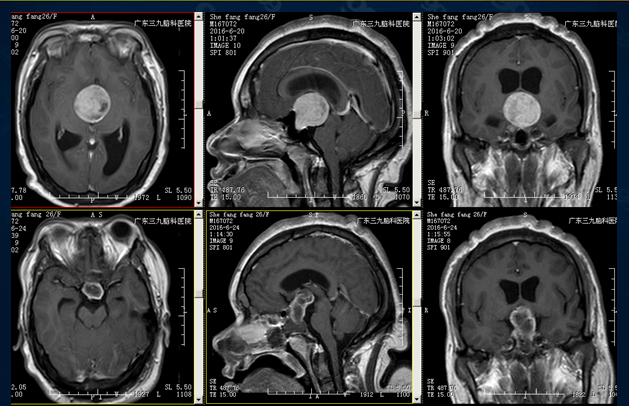

某女士,26岁,因视物模糊1年余,发作性头痛2周收治入院。既往史:既往体健,否认发热病史。诊断:1.垂体大腺瘤 2.梗阻性脑积水

手术前后磁共振增强对比

术后患者视力明显改善,头痛症状缓解,无尿崩,无脑脊液鼻漏,于27/6出院。定期门诊随诊。